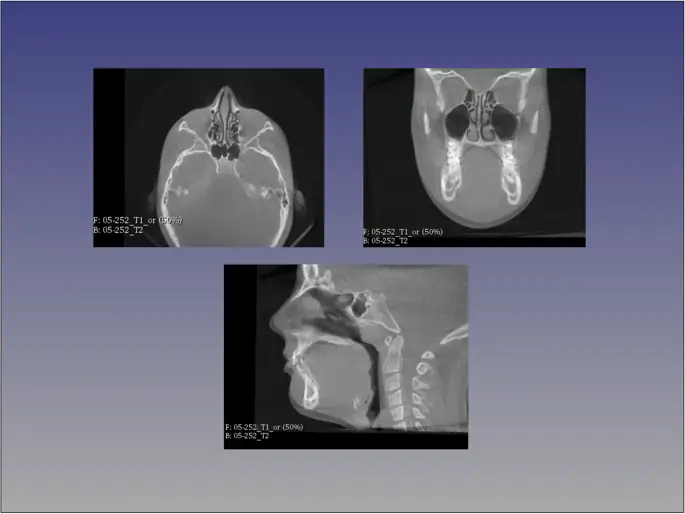

Рисунок 3

Аппроксимация краниального основания методом CMFreg / Slicer. Осевые, корональные и сагиттальные виды используются для наложения изображений до и после

Изображение в полном размере